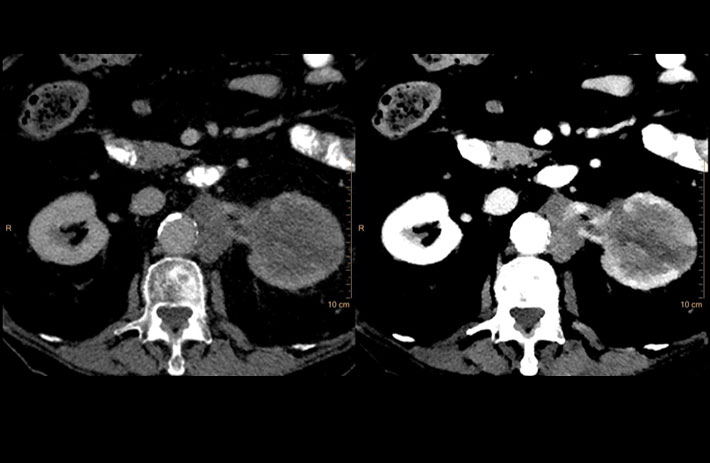

Mit dem Spektral-Detektor-CT werden Spektraldaten automatisch bei jedem Scan erfasst. Die Informationen stehen jederzeit auf der Scankonsole, der CT-Workstation sowie an jedem PACS-Arbeitsplatz zur Verfügung, sodass es nicht notwendig ist, den Patienten erneut zu scannen, bspw. wenn initial zufällige Anomalien festgestellt wurden. Dadurch profitieren Anwender durch eine höhere Diagnosesicherheit und weniger Nachuntersuchungen auf anderen bildgebenden Systemen. Unsere Fallsammlung zeigt, welchen klinischen Mehrwert der Spektral-Detektor-CT in unterschiedlichsten Anwendungsbereichen in der klinischen Routine bringt. Jede Woche gehen neue Fälle live.